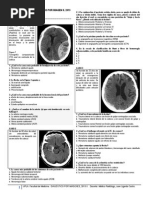

TC: masa sólida hiperdensa

con realce intenso y

homogéneo con contraste

(40%) o como lesiones

quísticas de tamaño variable

con un nódulo mural

hipercaptante (60%)

El nódulo mural capta contraste

de forma intensa; no hay

captación en la pared del

quiste.